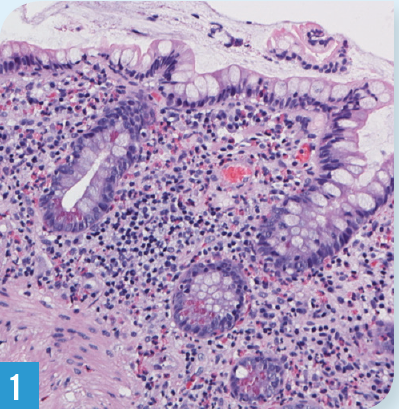

c difficile

05/21/2015

Gregory W. Rutecki, MD

In 2011, the number of serious healthcare-associated infections caused by the germ Clostridium difficile was estimated to be nearly 1.5 million.